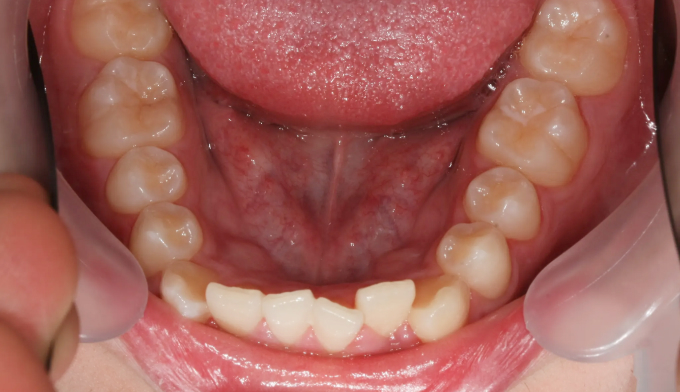

앞니가 돌출되어 있으면서 동시에 위 맨끝 어금니가 아래 어금니와 사선으로 물려있는 가위교합이 관찰됩니다.

가위교합은 음식물 섭취에 있어서도 비효율적이지만, 올바른 잇솔질을 하기가 어려워 구강위생에도 좋지 않아 교정이 필요합니다.

돌출입을 해소하고 동시에 가지런하지 못한 치열을 바르게 펴서 양치하기 좋은 상태로 만들어줍니다.